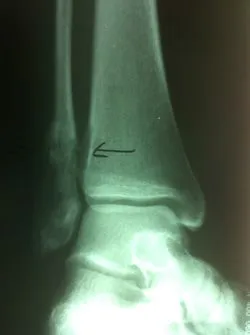

Stress fractures are often a clinical diagnosis as x-rays may be negative initially. The patient would typically experience pain and swelling across the top of the metatarsals. The pain would be mild in the morning. However, would get worse with weight-bearing. When x-rays are negative these problems are still treated as a fracture. X-rays taken 14-21 days after the injury will often show healing of the stress fracture by bone callus along the shaft of the bone.

Stress fractures that occur towards the end of the bone in the metaphyseal region often go nondisplaced after the healing process.

Stress fractures that occur in the midportion of the metatarsal can displace up, causing the potential for future problems in the metatarsal head region.